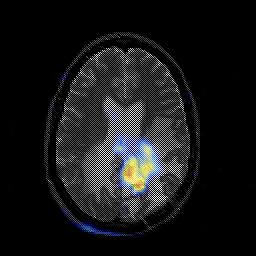

Glioblastoma multiforme overlay -- Slice #33

[Home][Help][Clinical][Tour 1][Tour 2][Tour 3] Slice 33